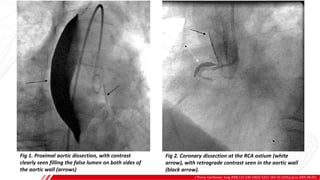

Fig 1. Proximal aortic dissection, with contrast

clearly seen filling the false lumen on both sides of

the aortic wall (arrows)

Fig 2. Coronary dissection at the RCA ostium (white

arrow), with retrograde contrast seen in the aortic wall

(black arrow).